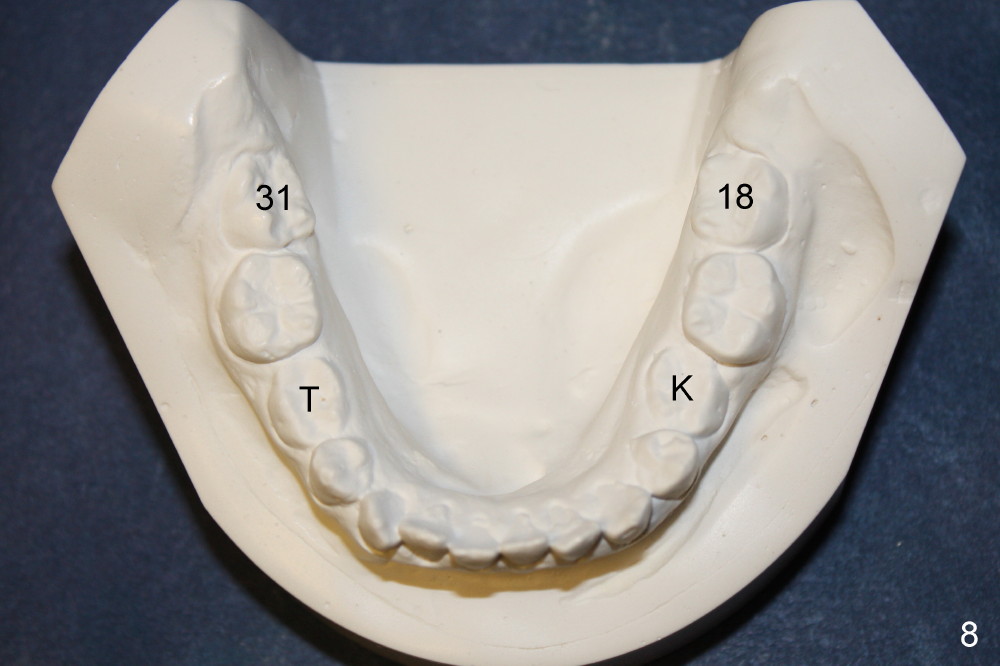

A 13-year-old Asian girl seeks orthodontic treatment for crowding. The lower 2nd bicuspids are congenitally missing (Fig.1,8), whereas the upper right one rotates 180° and the upper left is partially impacted (Fig. 1, 7). The lip muscles strain when the lips close (Fig.3). Orthodontic treatment started with extraction of four affected teeth (#4,13, K and T) 6 months ago. .018' niti wires are being used. Dental midlines do not coincide preop and intraop (Fig.4,4'). Pre-op front view shows that the upper dental midline coincides with the facial one (Fig.1'). There is Class I canine and molar relationship on the right (Fig.5,5',9,9'); open bite on the left (Fig.6,6',10,10').

Next steps: 1. Use elastics to close open bite on the left and to upright #31 (linguoversion, probably #18 to lesser degree) (Fig.8,8',9,9'); 2. Shift the lower midline to the left before closing 2nd bicuspid spaces. What is the best way to close spaces? Power chains for both arches or closed coil springs for upper and loop for lower (which is used for Tiffany Yue)? Since intraop profile is acceptable (Fig.2',3', as compared to Fig.2,3 (preop)), molars will be mesialized.

Update: The left open bite was closed less than one month by wearing elastics between upper and lower teeth (Fig. 6'''). The occlusal plane and midline improve (Fig.4''). Wires have gradually changed to .016x.016, .016x.022 and now .018x.025 with power chains. All the spaces are closed except the one in LR (Fig.7''-10''). What I cannot accomplish is to fix meisal (Fig.5'' (white line), 9'') and lingual (Fig.8'' arrows) inclination of LR molars, although elastic is instructed to be placed between UR7 buccal and LR7 lingual. The rectangular wires could be twisted to fix lingual inclination. Which should be done first: LR space or LR molar inclination? Click each figure for magnification.